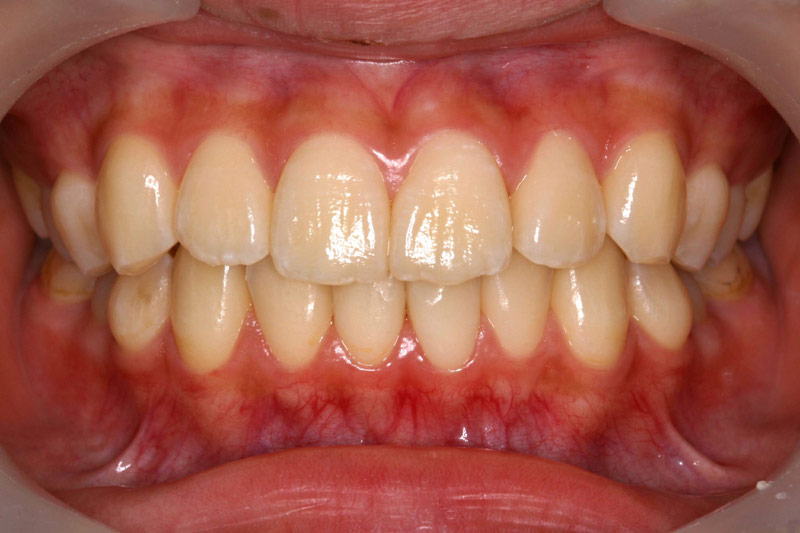

定期健診を継続し、虫歯に一回もなったことのない歯並びのきれいな患者さんが多く育っています。

子供達を健康で綺麗な歯並びの永久歯列に誘導していくことを咬合育成と言います。開業時から来院していた子供達を見ていて、どうしたら綺麗な歯並びにできるのかを研究してきました。最近その成果が上がるようになり多くの子供達が健康できれいな歯並びをもった大人になって来院するようになっています。対外的にも「講演・論文」のページにあるように各地の歯科大学や歯科医師会からその分野の講演を依頼されるようになり、いつのまにか須貝歯科医院の得意分野になってしまいました。永久歯への生え替わりの時期が最も重要な時期です。簡単な装置で歯並びを改善していくのですが患者さんによっては矯正専門医に紹介しなければならないケースもあります。その時は地元の信頼できる矯正専門医をご紹介しています。

上の前歯は下の前歯より前にないといけませんが、前歯の生え替わりの時に1本逆に生えてきました。そのままではきれいな歯並びにはなりそうもありません。この時が治療のタイミングです。簡単な矯正装置で改善しただけでその後きれいな永久歯列になりました。